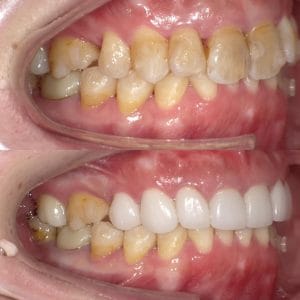

Case016 – インプラント

噛み合わせから審美的なところまで、トータルで治療させて頂いた患者様です。

ここまでやるとなると、できないクリニックもありますし、できるところでも年単位でかかってしまうクリニックが大半だと思いますが、今回は4月末にカウンセリングでご来院いただき、5月に治療をスタートして9月末には診療が終わっています。

治療回数や、治療期間がかかってしまうと、患者様も通院が辛くなったり疲れてしまったりしてしまうと思います。どんどん綺麗になっていく、食事がしやすくなっていくという実感がある方が患者様に楽しく治療に臨んでいただけると思うので、私は診療のスピード感を大切にしています。

トータルでやらせていただいたので、噛み合わせなどの機能面から外見などの審美性もかなり良くなり、患者様にも満足して頂けてよかったです。

治療期間 約4ヶ月